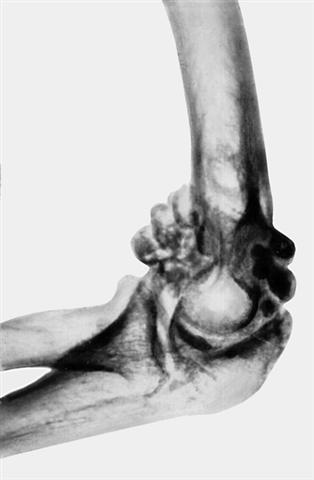

Рис. 12б). Рентгенограмма при хондроматозе локтевого сустава — боковая проекция.